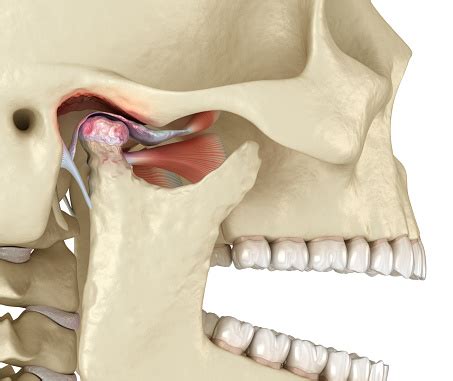

Артросиндесмология. Учение о соединениях костей...